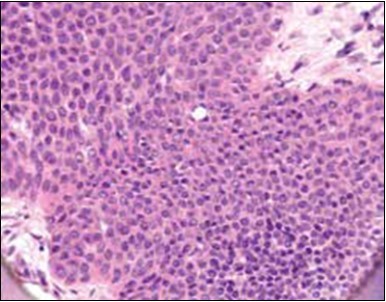

Figure 4.Cellular atypia, mitosis and focal necrosis in eccrine porocarcinoma(16).

Cellular atypia, mitosis and focal necrosis in eccrine porocarcinoma(16).